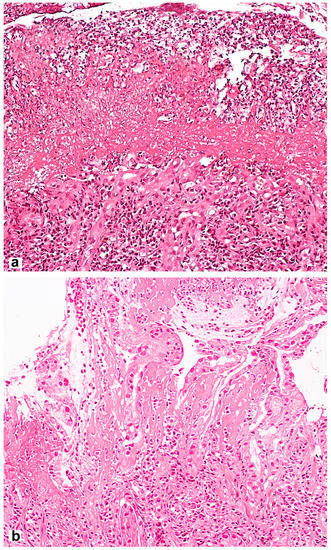

However, the long-term use of PPIs is associated with hyperplasia of enterochromaffin-like cells (ECL cells) and can provoke the formation of gastric fundus polyps [92] with specific morphological features (Figure 3). ECL cells play a key role in regulating gastric acid production through the release of histamine, which stimulates parietal cell acid secretion by binding to histamine-2 receptors. The risk of developing hyperplasia is likely to be influenced by both the duration and daily dose of PPIs, as well as the genetic factors of patients.

Figure 3.

Fundic gland polyp with cystically dilated glands and hyperplastic parietal cells spreading up to the pits. Hematoxylin and eosin stain. (a) ×40, (b) ×200.